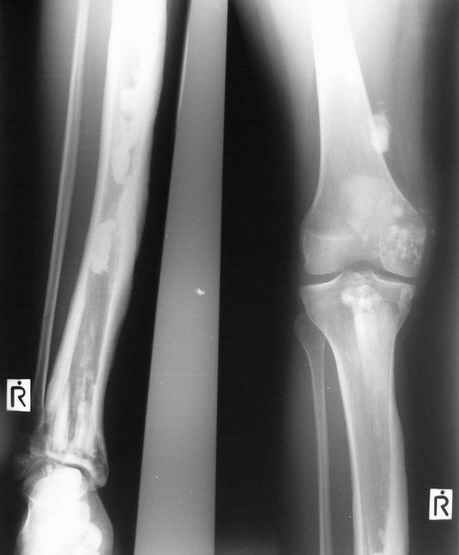

После меня выступал с новыми находками для своей коллекции Эмануэл Лакью Тесема, хирург-ортопед из Эфиопии: Мне понравились его находки:

Кто шустрый - при какой патологии встречается так называемые "суставы Шарко"?Второе приобретение доктора Эмануэла мне понравилось своим романтическим названием: Candle bone - <кость-в-виде-оплывающей-свечи> : Просто редкая патология:

VR>Второе приобретение доктора Эмануэла мне понравилось своим романтическим названием: Candle bone - <кость-в-виде-оплывающей-свечи> : Просто редкая патология:

Мелореостоз

Под названием "мелореостоз" описано около 50 случаев врожденного заболевания скелета, выражающегося в совершенно

своеобразном одностороннем остеосклерозе костей одной только конечности. Можно не сомневаться в том, что

мелореостоз встречается далеко не редко; мы наблюдали свыше 20 случаев. Вполне естественно, что отдельные новые

казуистические наблюдения, не вносящие в науку никаких новых фактов и не возбуждающие новых мыслей и обобщений,

остаются неопубликованными.

Остеосклероз при этом заболевании захватывает не всю кость по окружности, а простирается слегка волнистой

полосой вдоль длинной оси конечности (рис. 223, К), переходя через линию суставов на другие кости. Таким образом,

может оказаться пораженной целая верхняя или нижняя конечность или больший или меньший ее периферический участок,

например, часть лопатки, полуцилиндр плечевой кости, часть цилиндра лучевой кости и скелет II пальца вместе с

лежащими по этой оси участками запястных костей или же часть - медиальная или латеральная - бедренной,

болынеберцовой кости с продолжением и расширением процесса на предплюсневые и плюсневые кости и соответствующие

по длиннику фаланги одного или нескольких, но никогда не всех пальцев. Описавшие эту болезнь в 1922 г. Жоани

(Joanny) и Лери (Leri) сравнивают остеосклеротические полосы с картиной, напоминающей стекающий со свечи и

застывающий стеарин или воск, отсюда и название "мелореостоз" - "стекающая вдоль конечности кость".